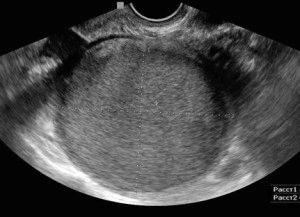

Однак найбільш інформативним способом вважається діагностична лапароскопія, що дозволяє візуально виявити захворювання, і в разі потреби взяти матеріал для гістологічного аналізу. Обстеження проводиться за допомогою оптичного устаткування. При виконанні процедури на передній стінці очеревини робляться невеликі проколи, через які в черевну порожнину вводиться апарат.